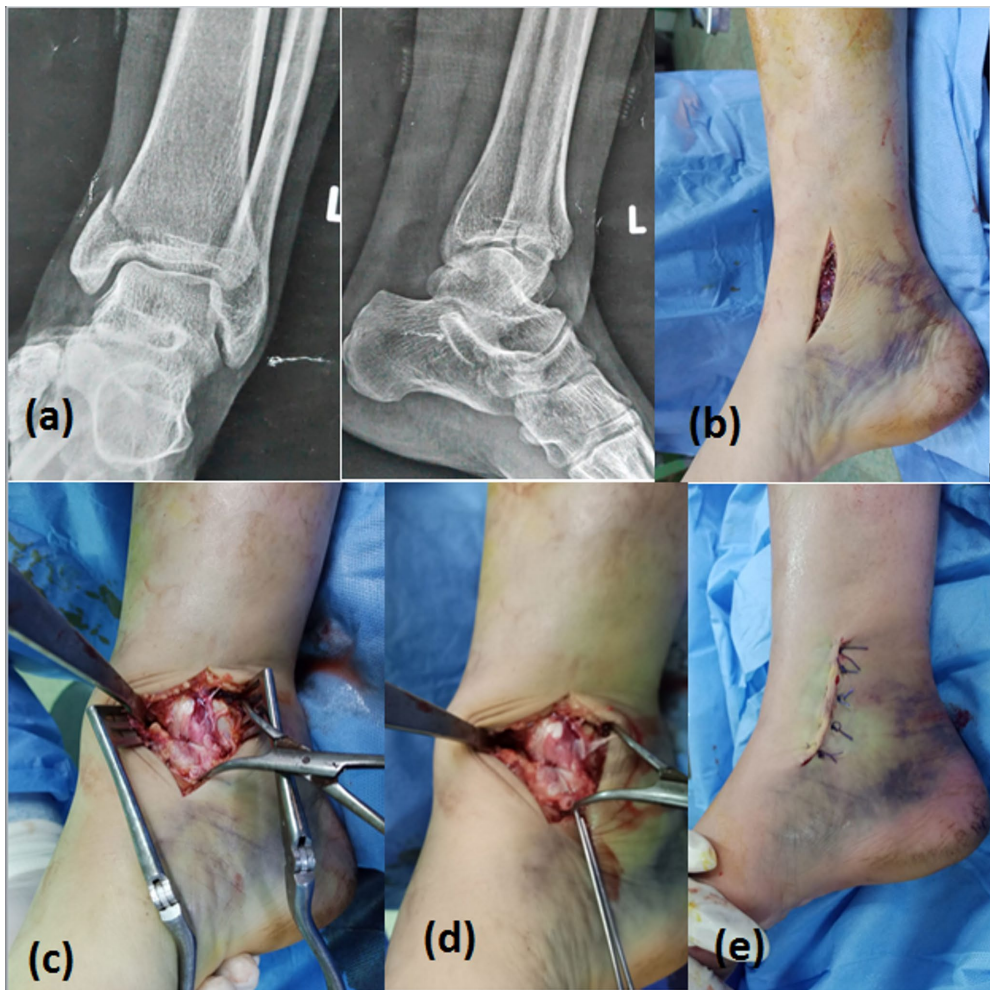

这项发表在《Archives of Orthopaedic and Trauma Surgery》的随机对照试验,首次在严格控制的条件下比较了两种术式——均采用相同的两枚4mm半螺纹空心松质骨螺钉固定。研究纳入50例Herscovici B/C型移位(>2mm)孤立性内踝骨折患者,通过计算机随机分为CRPF组和ORIF组,主要终点为影像学愈合时间和并发症发生率,次要终点包括FAAM(足踝功能量表)、AOFAS(美国足踝外科协会评分)和VAS疼痛评分等功能指标。

关键技术方法包括:1)计算机随机分组和评估者盲法设计;2)标准化手术操作——CRPF组采用尖头复位钳经皮复位,ORIF组采用3-5cm前内侧切口;3)统一使用两枚4mm半螺纹空心螺钉固定;4)通过X线片评估骨折愈合;5)采用FAAM、AOFAS等标准化功能评估工具。所有患者随访12-24个月,确保数据可靠性。